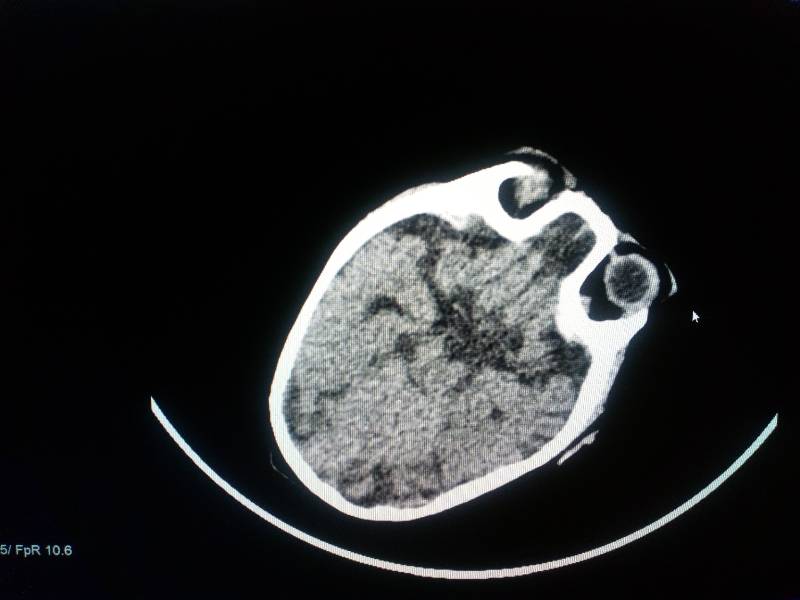

МРТ было сделано в 2009 году.

на фото стоит 16г

@мама лили, я фотала снимок мрт на телефон, там автоматом ставится дата. А само МРТ 2009 года.

У меня лобарная голопрозэнцефалия (это по поводу МПЩ). Гипоплазия мозолистого тела. Данные диагнозы по МРТ поставить было невозможно, только после того как я череп залезли эндоскопом и все увидели.

на снимке мпщ есть, я вам ее выделила. а то, что она с дефектом частичного срастания - это дело 5ое.

мама лили, посмотрите наше мрт, вся запись на диске, выбрала несколько фото

почему то одно только загрузилось